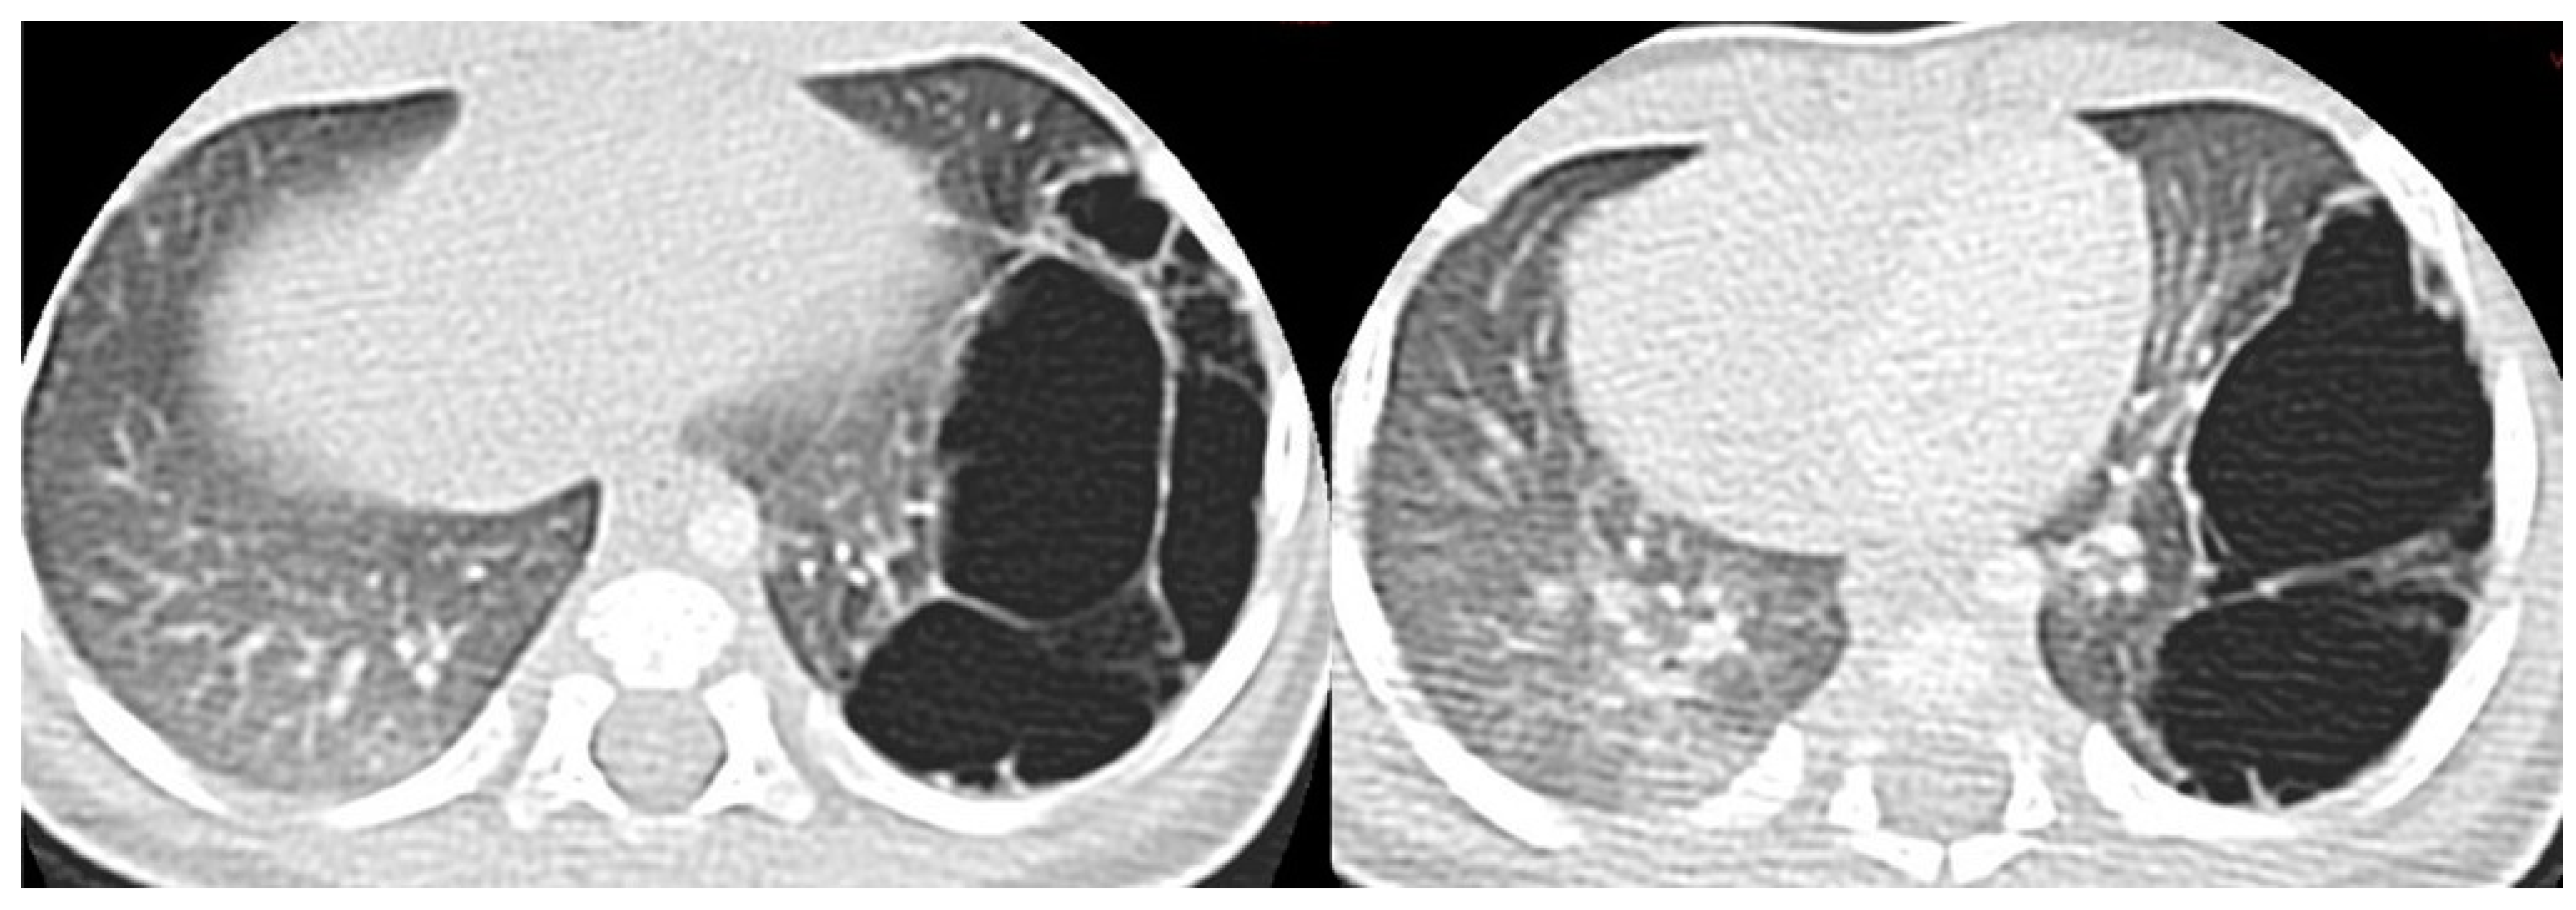

3.4.2. Congenital Pulmonary Airway Malformations

3.4.3. Congenital Lobar Hyperinflation

3.4.4. Congenital Bronchial Atresia

3.4.5. Bronchogenic Cysts

3.6.1. Pulmonary Sequestration